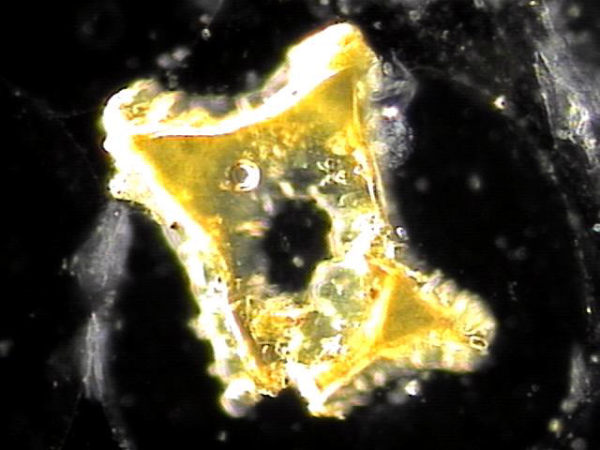

전립선과 사정관입구와 사정관 그리고 정낭과 정관의 표적 치료후 사정관 입구의 결석들이 치료된 현미경학적 자료 입니다.

This microscopic image was taken after targeted treatment of the prostate, the entrance of the ejaculatory ducts, the ejaculatory ducts themselves, the seminal vesicles, and the vas deferens.

The specimen shown here appears to be a calcified deposit or stone-like material (ejaculatory duct calculi). Such structures can form when shed epithelial cells, inflammatory debris, or proteinaceous substances accumulate and harden over time, often as a result of chronic inflammation or impaired circulation in the ducts.

For a more precise interpretation, consultation with international experts in urology, pathology, and andrology would be valuable, as their collective opinions could help confirm whether this represents a true ejaculatory duct stone, calcified tissue, or another type of mineralized deposit.

In practical terms for patients, this image suggests that treatment has helped dislodge and clear these obstructive materials, which is a positive sign for improving ductal flow and overall reproductive health.